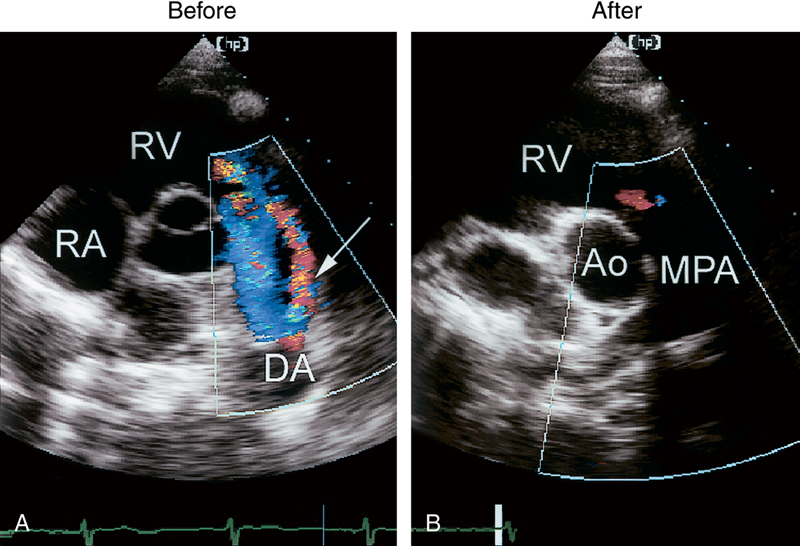

فحوصات تشخيصية لبعض امراض القلب والشرايين التاجية